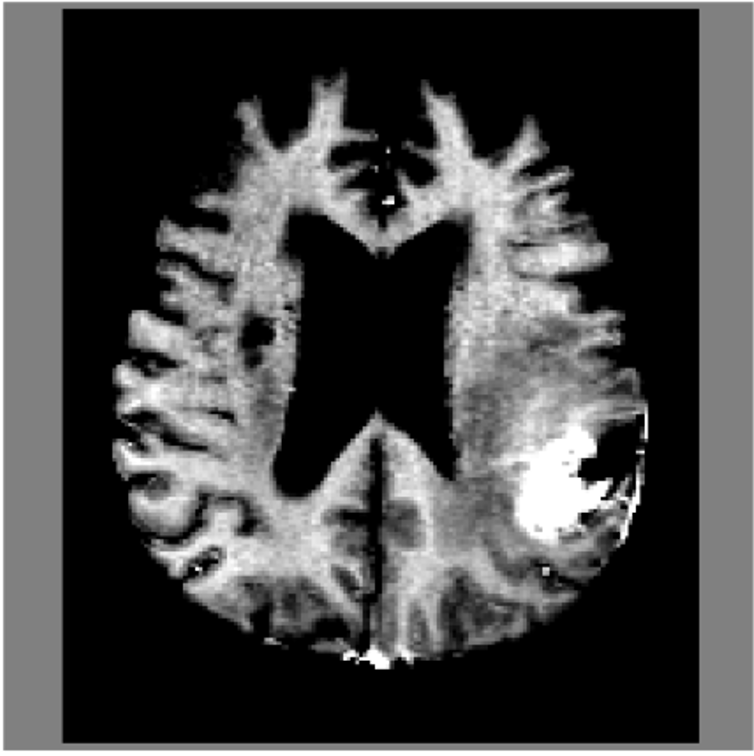

Refer to caption

Figure 4: Kaplan–Meier survival curves predicted by MeWM (left) and our method (right) on MU-Glioma-Post. Our approach produces a much clearer separation across risk strata, reflected by a lower log-rank pp-value of 0.0017 and a substantially higher C-index of 0.7856. Shaded regions denote 95% confidence intervals.

4.3 Survival Analysis

Figure 4 shows that our model achieves clearer separation across risk strata than the diffusion-based MeWM baseline. The survival curves diverge earlier with wider margins, yielding a lower log-rank pp-value (0.0017 vs. 0.0763) and higher C-index (0.7856 vs. 0.7013). We attribute this improvement to avoiding pixel-space diffusion reconstruction that tends to introduce stochastic artifacts, while latent-space modeling preserves clinically relevant structure and temporal consistency.